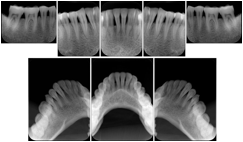

Intra-oral radiography typically involves acquisition of multiple images of various parts of the dentition. Many digital radiographic systems offer customized templates that are used for displaying the images in a study on the screen. These templates may also be referred to as mounts or view sets. The Structured Display Object represents a standard method of encoding and exchanging the layout and intended display of Structured Displays. A structured display object created in this manner could be stored with a study and exchanged with images to allow for complete reproduction of the original exam.

1. A patient visits a General Dentist where a Full Mouth Series Exam with 18 images is acquired. The dentist observes severe bone loss and refers the patient to a Periodontist. The 18 images from the Full Mouth Series along with a Structured Display are copied to a DICOM Interchange CD and sent with the patient to see the specialist. The Periodontist uses the CD to open the exam in his Dental Radiographic Software and consults via phone with the General Dentist. Both are able to observe the same exam showing the images on each user's display using the exact same layout.

Intra-oral Full Mouth Series Structured Display

Figure OO-1. Intra-oral Full Mouth Series Structured Display